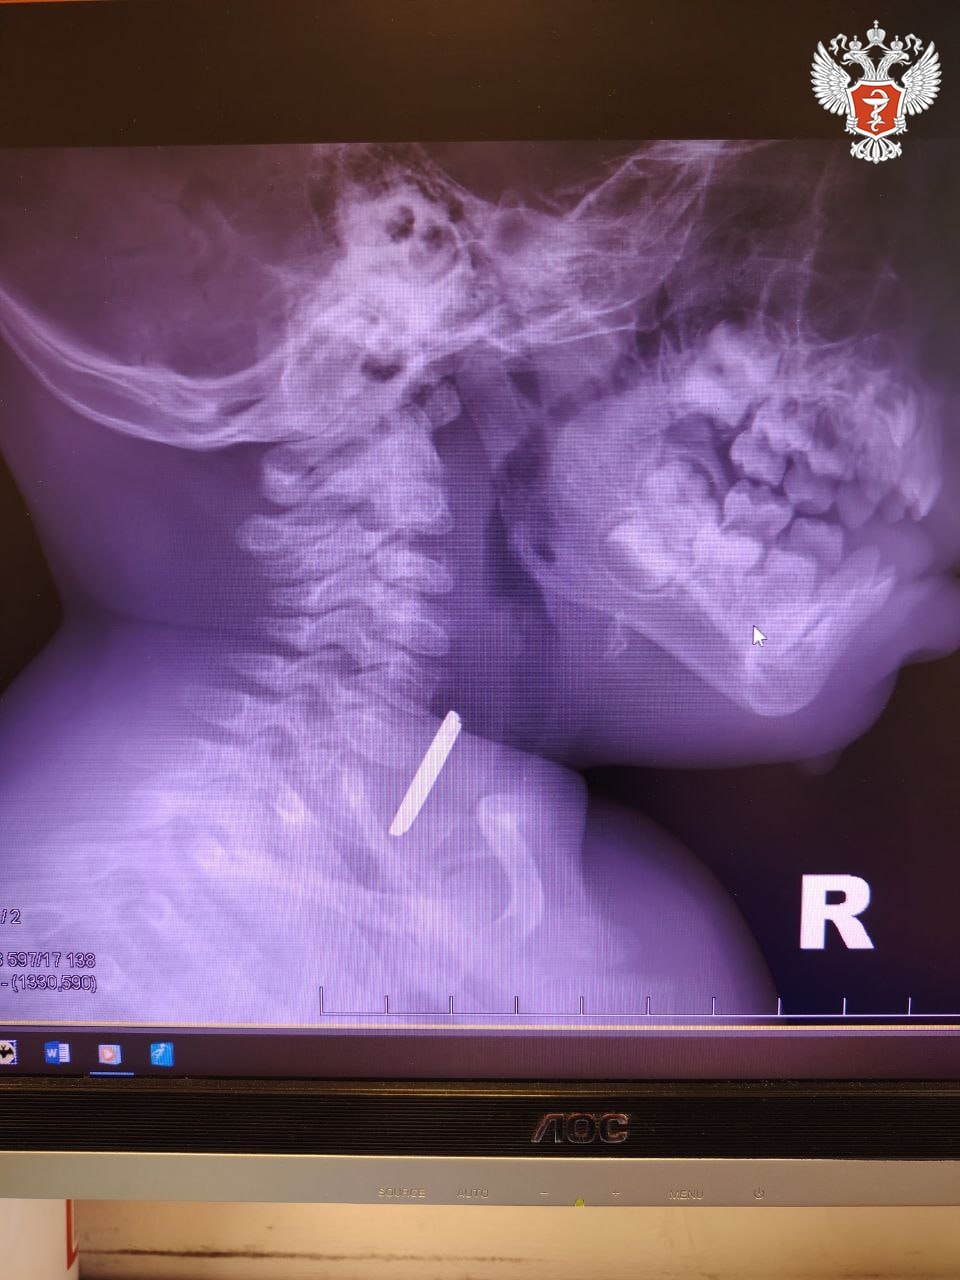

Годовалый ребенок поступил в Нижневартовскую окружную клиническую детскую больницу с затруднённым глотанием и слюнотечением. Врачи выполнили рентген и выявили круглое инородное тело в верхней трети пищевода.

➡ Специалисты приняли решение о проведении экстренной операции и извлекли батарейку, но предмет успел нанести вред здоровью пациента.

— Батарейка повредила стенку пищевода, вызвав глубокий электрохимический ожог, занимающий половину просвета пищевода. Учитывая тяжесть состояния от полученной травмы, ребенок был госпитализирован в отделение реанимации, где проводилась интенсивная терапия. После стабилизации состояния малыша перевели в детское хирургическое отделение, где было продолжено ранее начатое консервативное лечение, — рассказал детский хирург Нижневартовской окружной клинической детской больницы Вячеслав Воронин.